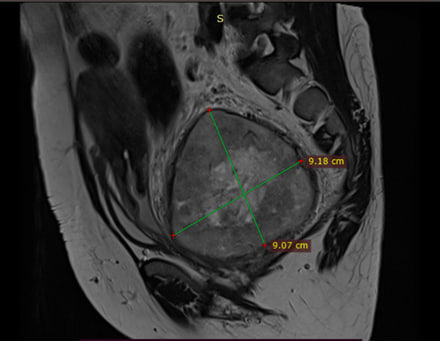

On T2 MRI showing a 9.18 x 9.07 cm fairly defined, heterogenous mass in pelvis/presacral region with prominent internal and surrounding vessels causing rightward displacement and compression of rectum. No enlarged lymph nodes.